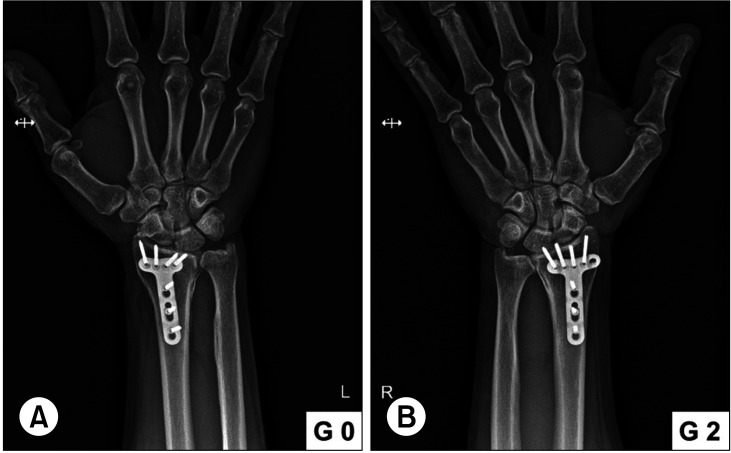

背景:创伤后骨关节炎(OA)是桡骨远端骨折(DRFs)的并发症之一。累及乙状窦切迹(SN)是一个危险因素,但很少有研究支持这一点。在本研究中,我们假设SN受累会影响手术治疗的DRFs的放射学和临床结果,并且根据SN受累程度的不同会有差异。方法:作者回顾了在我院接受手术治疗的DRF患者,并进行了超过5年的随访。根据SN受累情况将患者分为两组。所有患者在最后一次随访时均接受术后x线平片检查,以评估远端尺桡关节(DRUJ)创伤后骨性关节炎。在SN受累组的计算机断层扫描(CT)上,测量关节台阶和间隙距离。使用Knirk和Jupiter放射学标准对创伤后骨关节炎进行分级。临床评估方法包括握力、手腕活动度、疼痛视觉模拟量表评分、手臂、肩部和手部残疾问卷以及改良梅奥手腕评分。结果:放射学上,SN受累组的DRUJ OA评分明显更高。CT扫描测量的台阶距离和间隙距离显示与分级无显著相关性。两组临床结果无显著差异。结论:在至少5年的随访中,SN受累对DRF患者的临床结果没有影响。然而,放射学上,骨性关节炎分级明显高于SN受累组。因此,在伴有SN累及的DRF病例中,临床结局无明显差异,但有必要向患者说明,未来可能发生创伤后DRUJ关节炎。

Methods: The authors reviewed patients who underwent surgical treatment for DRF at our institution and were followed up for over 5 years. The patients were divided into 2 groups based on SN involvement. All patients underwent postoperative plain radiographs at the last follow-up to evaluate posttraumatic OA at the distal radioulnar joint (DRUJ). On computed tomography (CT) scans of the SN involvement group, articular step-off and gap distance were measured. Posttraumatic OA was graded using the Knirk and Jupiter radiographic criteria. For clinical evaluation, grip strength, wrist range of motion, pain visual analog scale score, Disabilities of the Arm, Shoulder, and Hand questionnaires, and Modified Mayo Wrist Score were assessed.

Results: Radiologically, the DRUJ OA grades were significantly higher in the SN involvement group. The step-off and gap distance measured on CT scans revealed no significant correlation with the grades. Clinical outcomes were not significantly different between the 2 groups.